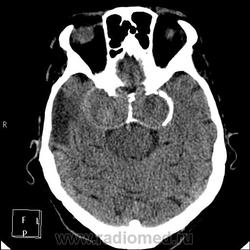

А контраст почему не делали? Больше похоже на тромбированные аневризмы

Неужели такие аневризмы? Бывает же! А сканы с контрастом есть?

Макроаденома гипофиза с интра-эндо-супра-и латероселлярным ростом,инвазией кавернозных синусов и зрительной хиазмы.

В первую очередь подумала бы о менингиоме бугорка турецкого седла или передних наклоненных отростков. Дифференцировала бы с краниофарингиомой но смущает форма.

Да простят моё нахальство уважаемые специалисты КТ. Я вижу тут огромные инкапсулированные узлы расположенные почти симметрично справа и слева от турецкого седла, которое разрушено узлом поменьше. Латеральные злы продавливают дно средней черепной ямы. По-видимому, здесь доброкачественная опухоль типа «аденома», исходящая из гипофиза и давно растущая. Обызвествление есть не только в капсулах узлов, но и в их толще (очаговое). При таких размерах узлов и косных разрушениях, нет сомнения, пострадали и зрительные нервы.

Цифровых и плёночных доказательств на руках нет. Опухоль диагностирована в 2004 году, размером "с вишню", дебютировала птозом века правого глаза, умеренной головной болью в лобной области слева и постепенным снижением зрения, катаракта. Пациентка с трезвом уме и превосходной памяти (на мой субъективный взгляд))). В выписке результаты КТ, МРТ: неоперабельная опухоль селлярно-параселлярной области с прорастанием кавернозных синусов, аневризма сифона внутренних сонных артерий. Цитологию НЕ брали.

Не совсем понятно, опухоль + аневризма или как?

Да, опухоль, в толще которой аневризма сифона ВСА. Причем с обеих сторон.

Аневризмы с обеих сторон или опухоль?

И то, и другое. Доказать без контрастирования не могу. Когда сама впервые увидела, анамнеза не знала, подумала о двусторонней аневризме. И не угадала.

Насчет опухоли у меня большие сомнения. То что седло растянуто, еще не показатель. Седло увеличивается в размерах даже при гипертонии,а тут такие аневризмы. Самой опухоли не видно, в просвете турецкого седла медиальные полюса аневризм. Ну впрочем не так это важно, интерес чисто теоретический, да и верификации видимо не будет. Спасибо большое за демонстрацию.

Случай-таки не верифицированный. Сочетание опухоли с аневрзмами - это очень странно. Боюсь, тут какая-то путаница.